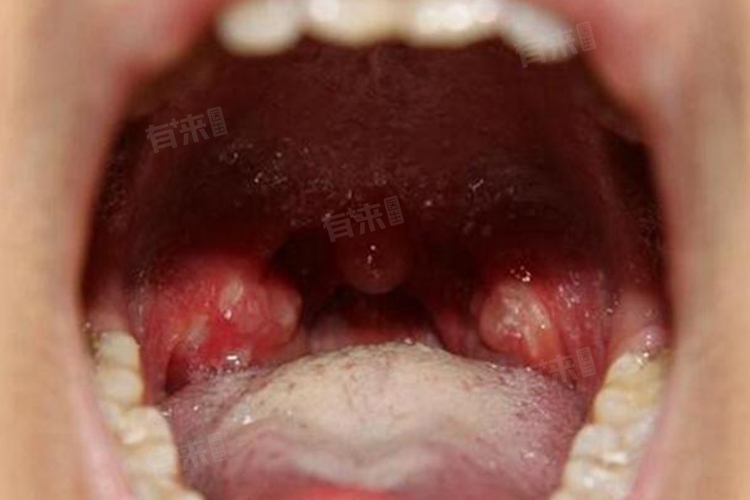

- 密切观察症状变化:留意发热、咽痛、咳嗽等症状变化。若体温持续不退、咽痛加剧、出现呼吸困难等,可能病情加重,需立即就医。关注口腔疱疹情况,有无破溃、感染迹象。